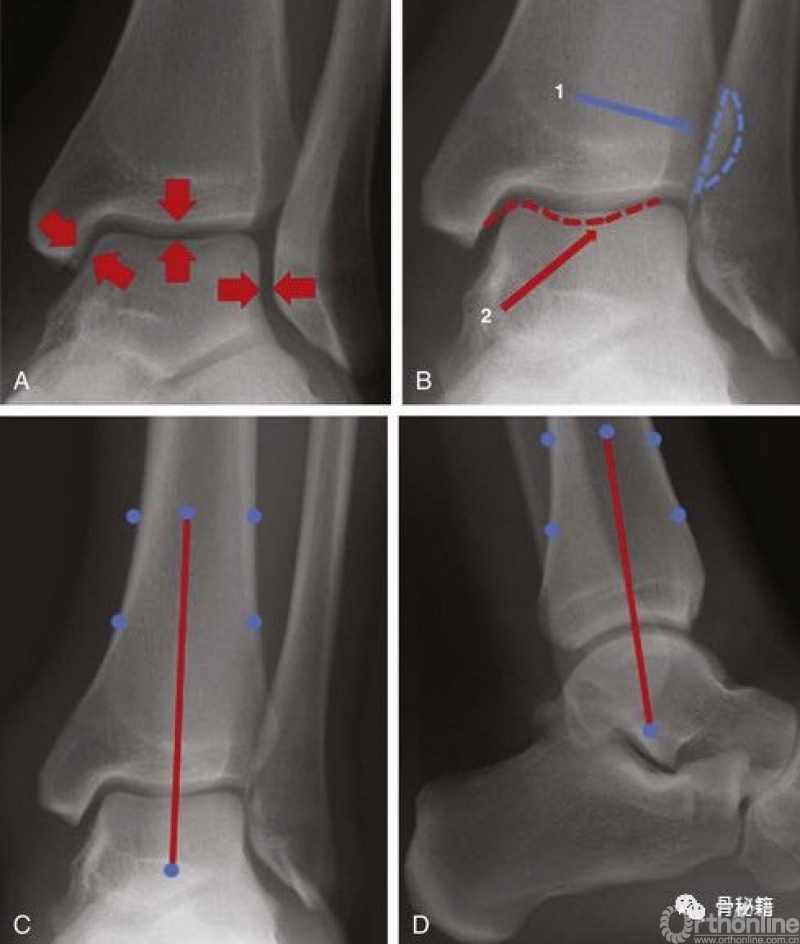

胫骨远端的关节面,注意与踝部的关节。

A,关节面应在整个关节中等距(箭头)。B,腓骨与远端胫骨(1)和后踝(2)关节。

C和D,正侧位腿的中轴(红线)穿过穹顶的中心和距骨。

对于术后片子,我们一定要进行评估,看看腓骨到底有没有解剖复位,距骨有没有外移,踝关节骨折很注重这点,pilon也不例外。

那篇著名的文献:距骨外移1mm,接触面积减少42%。